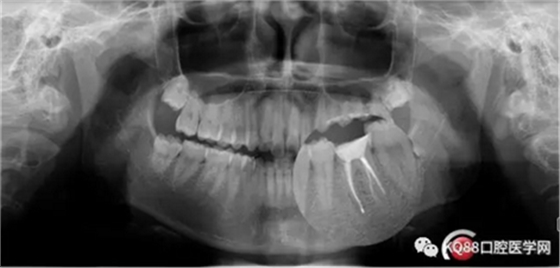

首先預(yù)備樁道,樁道預(yù)備完成,用樹脂封閉根管口。嵌入兩根纖維樁。樁核粘結(jié)劑做基。

3M樹脂修復(fù)缺損。舌側(cè)電刀切齦,暴露齦壁,修整,制備。單線排齦,取模。

下次戴上全鋯全冠,整個治療修復(fù)過程就完成了。